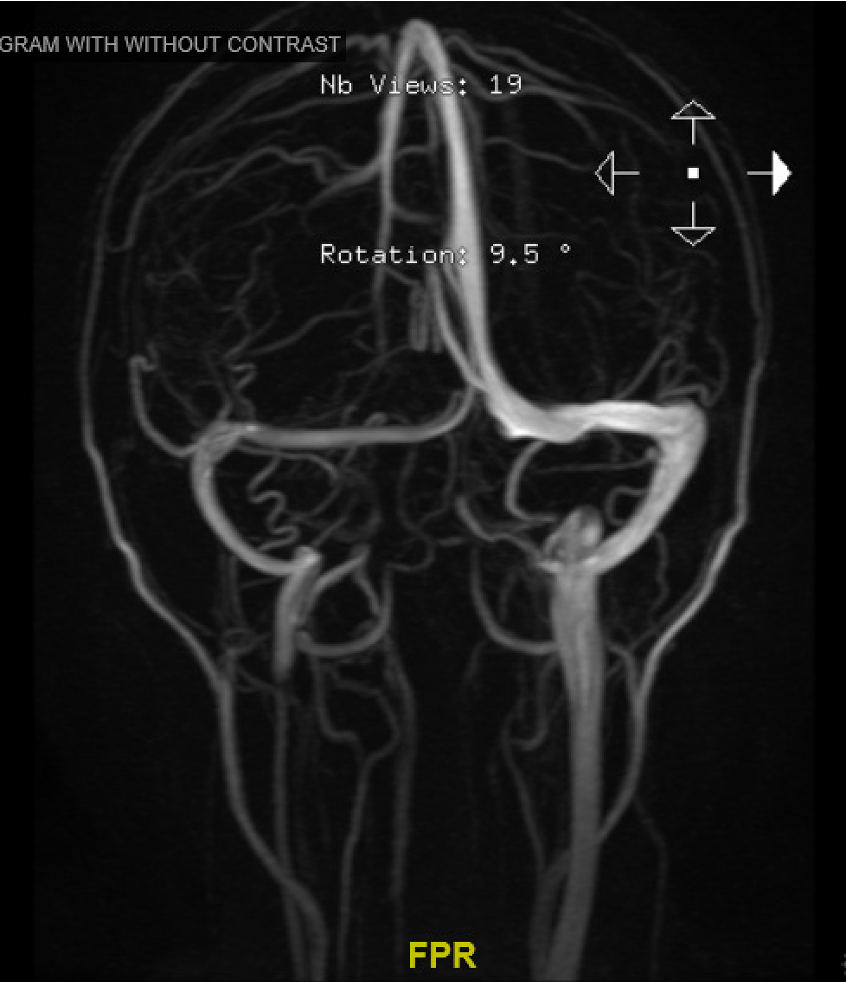

MRV